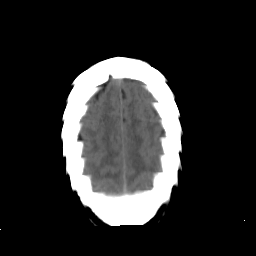

Stroke CT #3 -- Slice #21

[Home][Help][Clinical] Slice 21